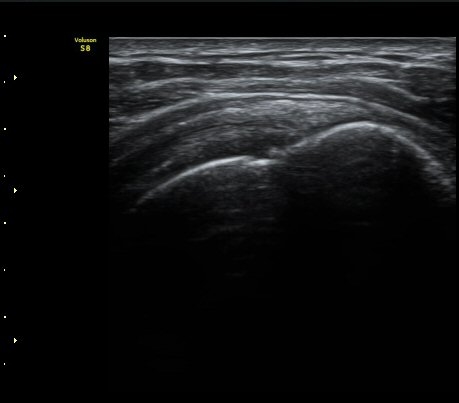

±Ø»ó°Ç Á¾´Ü¸é°Ë»ç¿¡¼­ ´ë°áÀý°ú »ó¿Ï°ñµÎ ÀÌÇàºÎÀ§¿¡ ÇÇÁú°ñ ¿¬¼Ó¼º ¼Ò½ÇÀ» º¸ÀÓ(±×¸² 3, 4, 5)